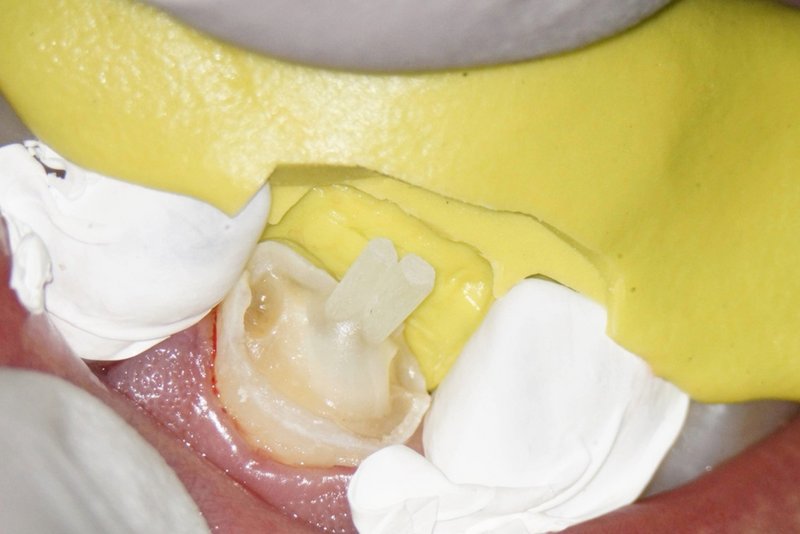

Wurzelkanalfüllung mit doppeltem Stiftaufbau. Gut erkennbar ist der vom Prothetiker angefertigte Silikonschlüssel für den Kompositaufbau.